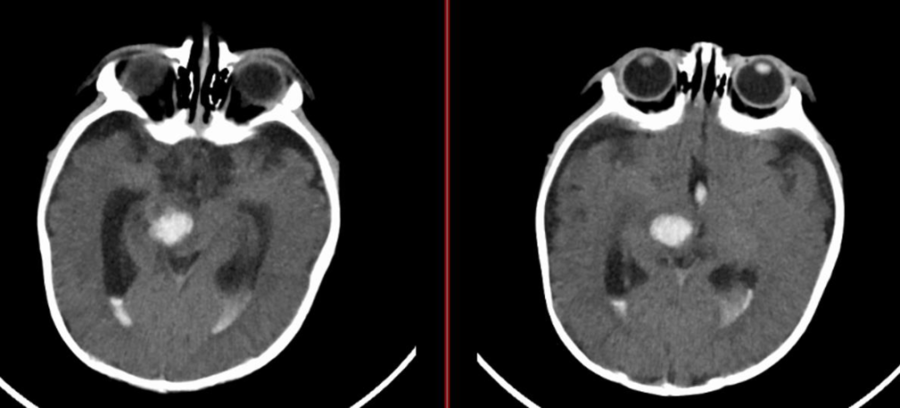

颅脑CT提示脑干、丘脑出血破入脑室

经过新生儿重症监护室积极治疗后,甜甜的病情暂时趋于稳定,但颅脑MRI及CTA检查结果显示情况不容乐观,脑干、丘脑出血破入脑室。虽然血肿使组织结构不易辨清,但经验丰富的王广宇仍从影像学上“嗅出”了异常。磁共振及CTA检查结合临床,考虑“脑干海绵状血管瘤出血”。